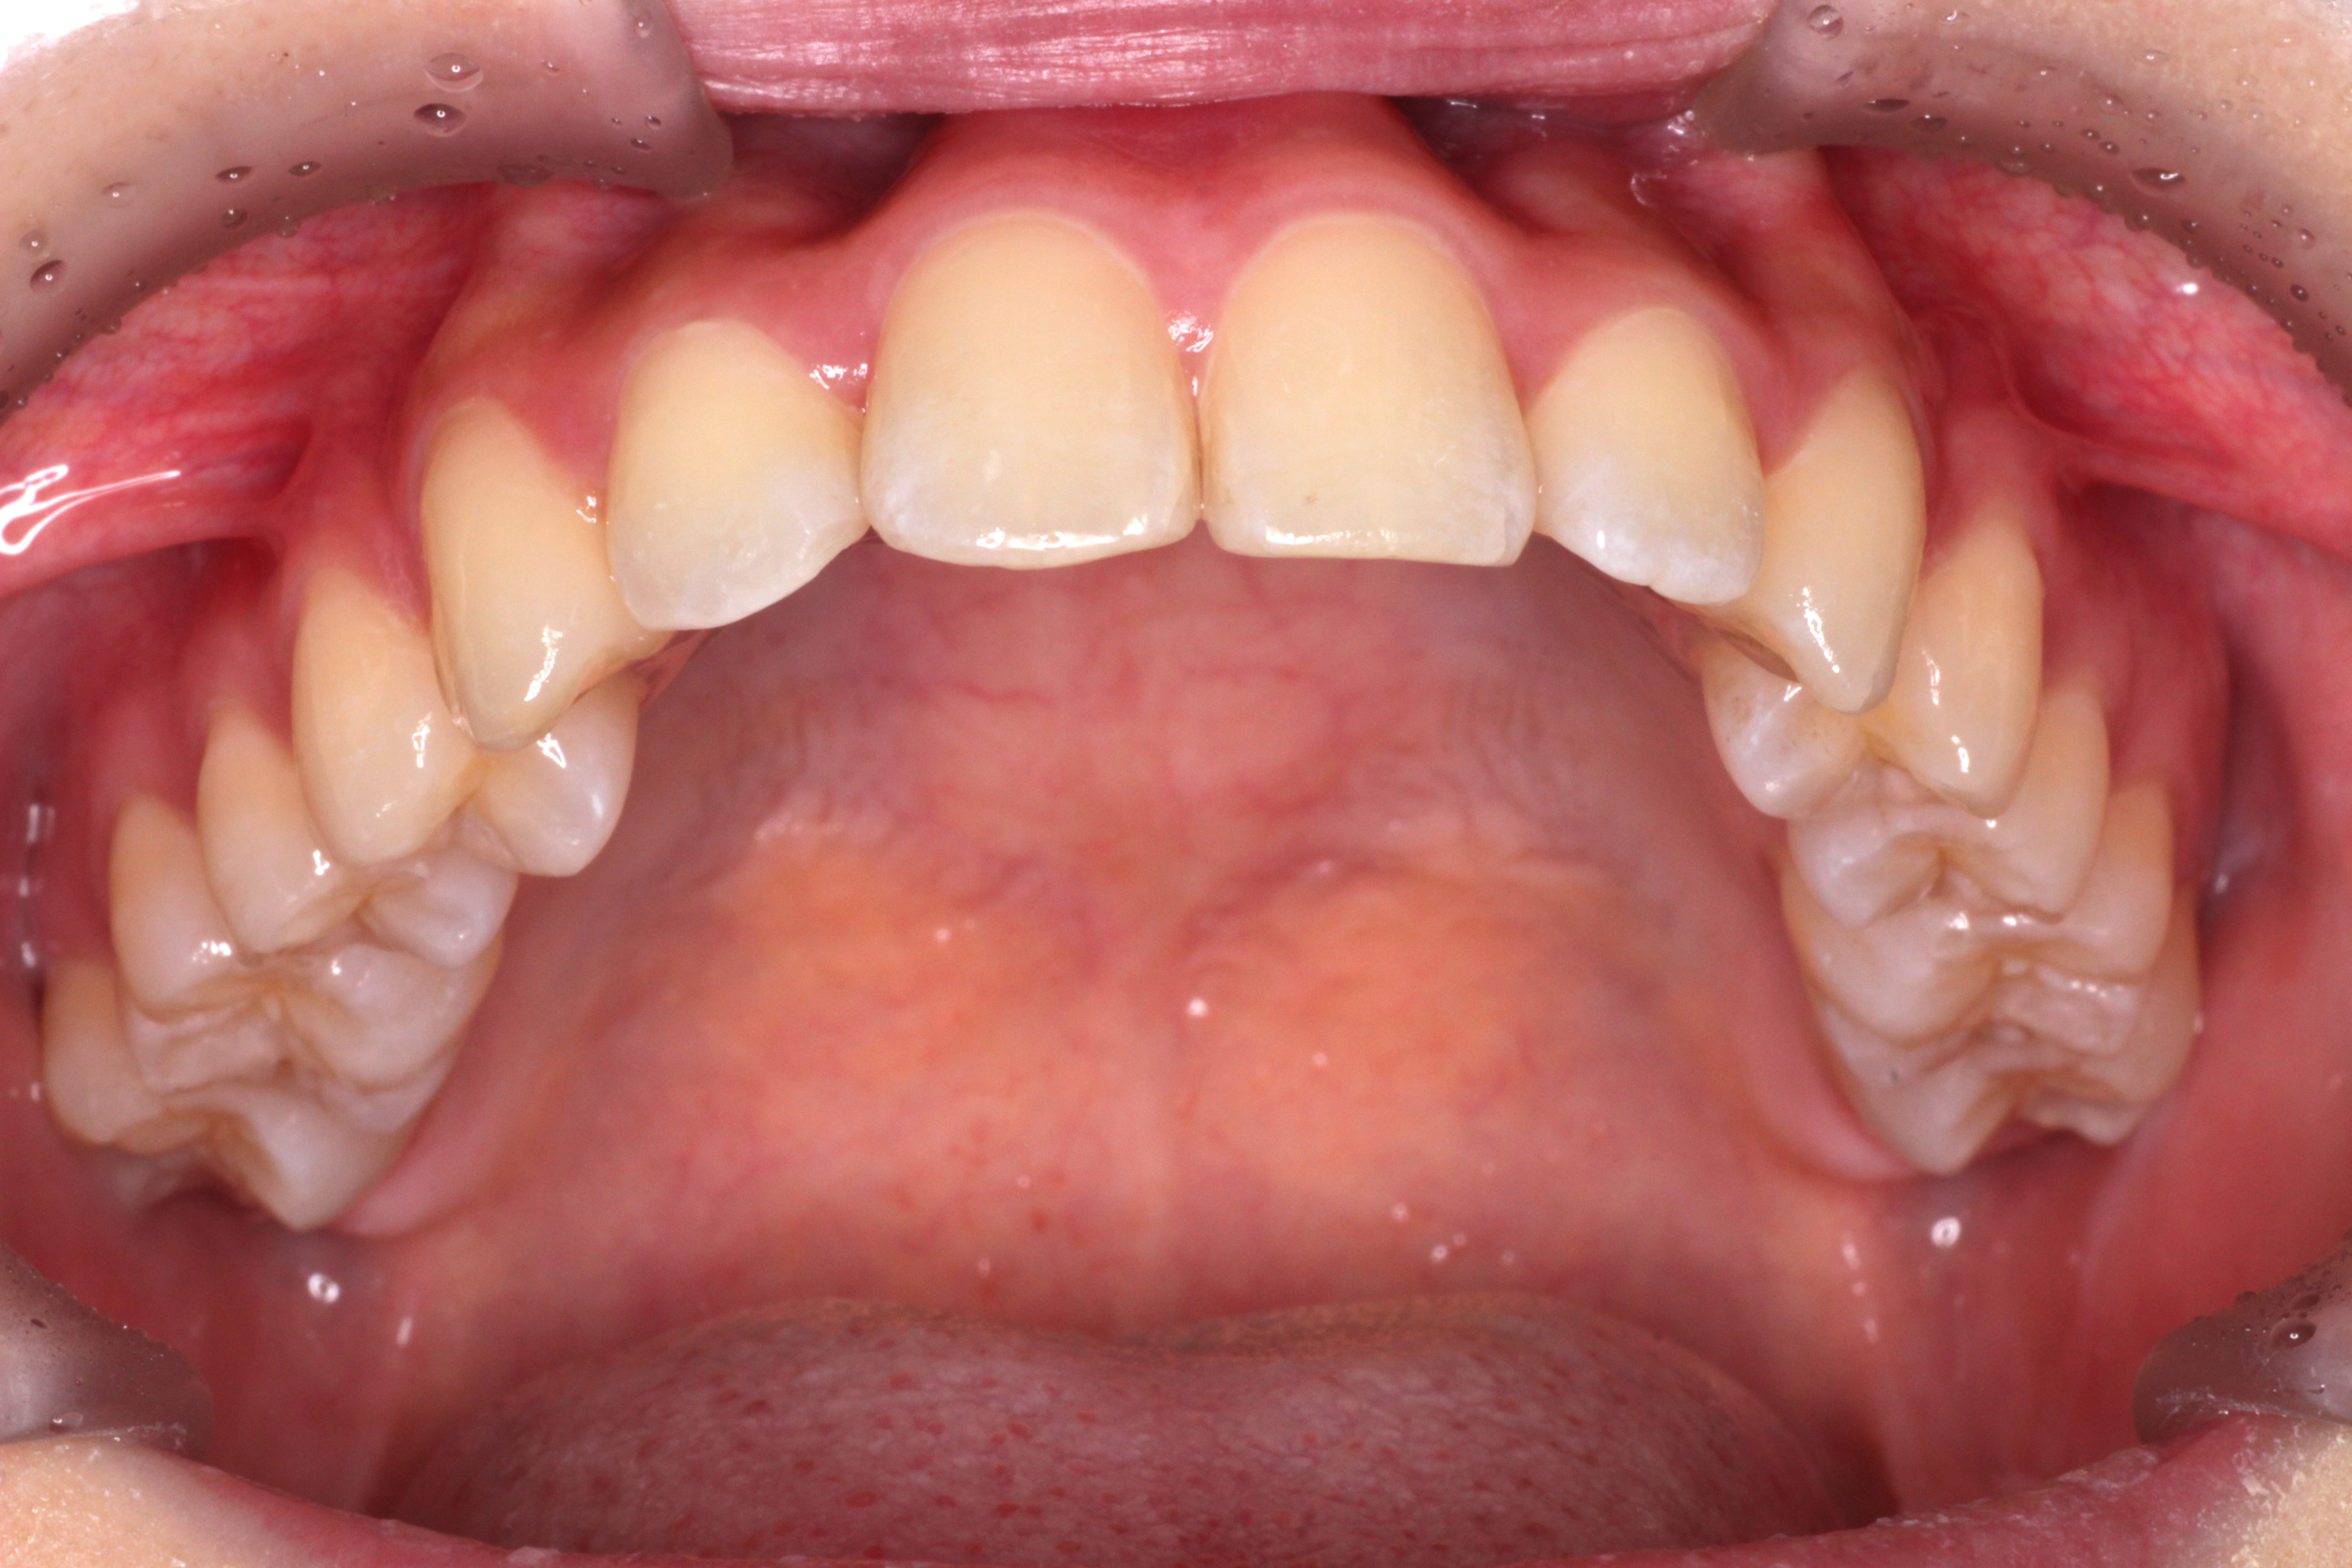

初診時のお口の中の状態です。↓

お口の中の状態としては

⑴咬み合わせが深い。(上の歯がかぶさっていて、下の歯が見えません。)

⑵右下の前から2番目の歯が叢生で歯列に入っていません。

⑶右上の前から2番目の歯が下の歯より前にありません。

診断:上顎前突・前歯部叢生